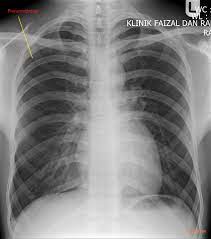

Pneumothorax / Case Report Covid 19 Associated Bilateral Spontaneous Pneumothorax A Literature Review In The American Journal Of Tropical Medicine And Hygiene Volume 103 Issue 3 2020 / Tension pneumothorax most commonly occurs in people with penetrating chest injuries.. This may be caused by physical trauma to the lung, such as a wound. Pneumothorax nursing interventions, treatment, pathophysiology nclex review for the different types of pneumothorax: There are several variations of pneumothorax. Pneumothorax is the medical term for a collapsed lung, a condition in which air or gas is trapped in the space surrounding the lungs causing the lungs to collapse. Also known as pneumothorax, collapsed lung is a rare condition that may cause chest pain and make it hard to breathe.

This is termed spontaneous pneumothorax. Pneumothoraces can be even further classified as simple, tension, or open. Pneumothorax nursing interventions, treatment, pathophysiology nclex review for the different types of pneumothorax: Pneumothorax, also called a collapsed lung, is when air gets between one of your lungs and the wall of your chest. It is reasonably common and has many different causes.

Scielo Brasil Pneumothorax As A Late Complication Of Covid 19 Pneumothorax As A Late Complication Of Covid 19 from minio.scielo.br In tension pneumothorax, patients are distressed with rapid laboured respirations, cyanosis, profuse diaphoresis, and tachycardia. The definition of a pneumothorax is an accumulation of air outside the lungs, but inside the chest wall. Tension pneumothorax most commonly occurs in people with penetrating chest injuries. In a healthy body, the lungs are touching the walls of the chest. Patients with a pneumothorax typically report dyspnoea and chest pain. A pneumothorax occurs when air leaks into the space between the lung and chest wall (called the pleural space). A small pneumothorax may cause few or no symptoms. Pneumothorax occurs when air enters the space around your lungs (the pleural space).

Other signals that the problem may be a collapsed lung are: Normally, the outer surface of the lung sits next to the inner surface of the chest wall. The lung and the chest wall are covered by thin membranes called pleura. It occurs when air accumulates between the parietal and visceral pleura inside the chest. Pneumothoraces can be even further classified as simple, tension, or open. A pneumothorax is an abnormal collection of air in the pleural space between the lung and the chest wall. Pneumothorax is defined as the presence of air or gas in the pleural cavity (ie, the potential space between the visceral and parietal pleura of the lung), which can impair oxygenation and/or. A pneumothorax occurs when air leaks into the space between your lung and chest wall. The pressure causes the lung to give way, at least partly. Pneumothorax is classified as spontaneous or traumatic. Hemothorax occurs when there is blood in that. This air pushes on the lung, which makes it collapse. The air accumulation can apply pressure on the lung and make it collapse.

Pneumothorax Physiopedia from www.physio-pedia.com Women with catamenial pneumothorax have recurrent episodes of pneumothorax that occur within 72 hours before or after the start of menstruation. This air pushes on the outside of your lung and makes it collapse. A hole might grow in the surface of the lung. Pneumothorax (sometimes called collapsed lung) is a health problem where air or gas is in the pleural space (the space between the lung and the pleura). The pressure causes the lung to give way, at least partly. Human beings have a complete and strong mediastinum so that pneumothorax is generally unilateral and thus not a serious problem. A special form of the traumatic pneumothorax is the iatrogenic pneumothorax occurring as a result of diagnostic and/or therapeutic interventions. A pneumothorax is a collapsed lung.

While secondary pneumothorax is caused by an underlying pulmonary disease, the spontaneous type occurs in healthy individuals without obvious cause. When there is no apparent cause, the condition is known as spontaneous pneumothorax. Other signals that the problem may be a collapsed lung are: Pneumothorax is classified as spontaneous or traumatic. Normally, the outer surface of the lung sits next to the inner surface of the chest wall. There are several variations of pneumothorax. It occurs when air accumulates between the parietal and visceral pleura inside the chest. A tension pneumothorax can cause complete collapse of the nearby lung and can push the heart and major blood vessels to the other side of the chest. A collapsed lung requires immediate medical care. Patients with a pneumothorax typically report dyspnoea and chest pain. This air pushes on the outside of your lung and makes it collapse. The lung and the chest wall are covered by thin membranes called pleura. Also known as pneumothorax, collapsed lung is a rare condition that may cause chest pain and make it hard to breathe.

Patients with a pneumothorax typically report dyspnoea and chest pain. Pneumothoraces can be even further classified as simple, tension, or open. Pneumothorax is defined as the presence of air or gas in the pleural cavity (ie, the potential space between the visceral and parietal pleura of the lung), which can impair oxygenation and/or. In a healthy body, the lungs are touching the walls of the chest. The definition of a pneumothorax is an accumulation of air outside the lungs, but inside the chest wall. It is reasonably common and has many different causes. A pneumothorax is a collection of air outside the lung but within the pleural cavity. A pneumothorax can be a complete lung collapse or a collapse of only a portion of the lung. A pneumothorax occurs when air leaks into the space between the lung and chest wall (called the pleural space). This air pushes on the lung, which makes it collapse. Also known as pneumothorax, collapsed lung is a rare condition that may cause chest pain and make it hard to breathe. A large pneumothorax can squash the lung and cause it to collapse. This is termed spontaneous pneumothorax.